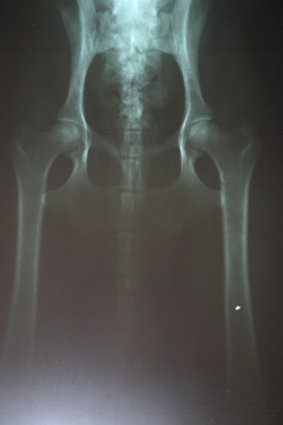

Dusty Röntgenaufnahme * HD-A